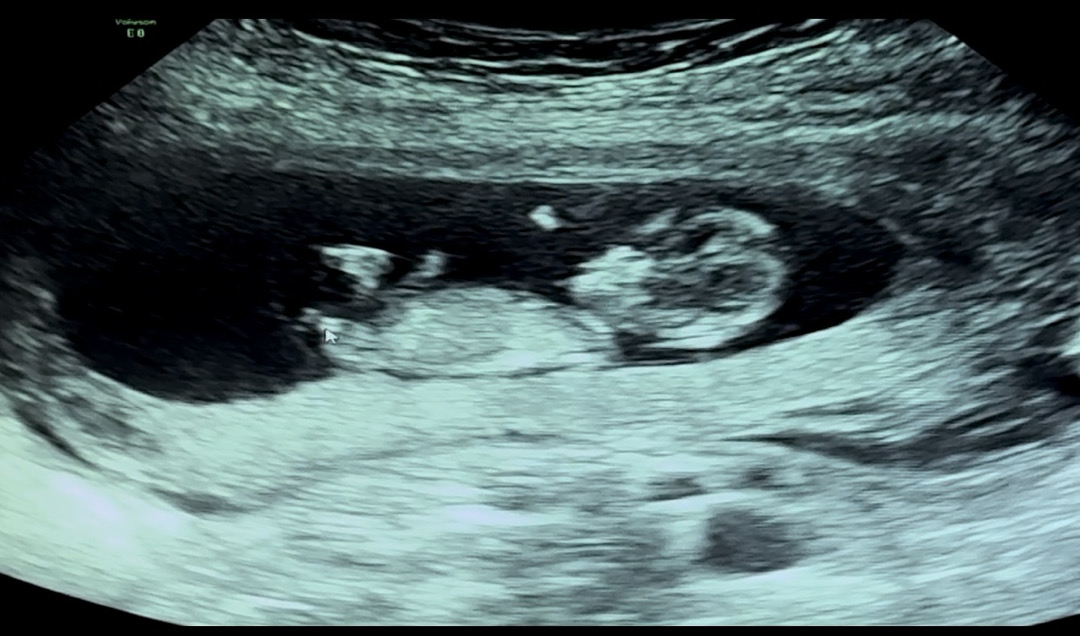

12주 각도법 같이봐주실 분 !

화살표가 생식기래요 각도 어때보이시나요 ㅠㅠ